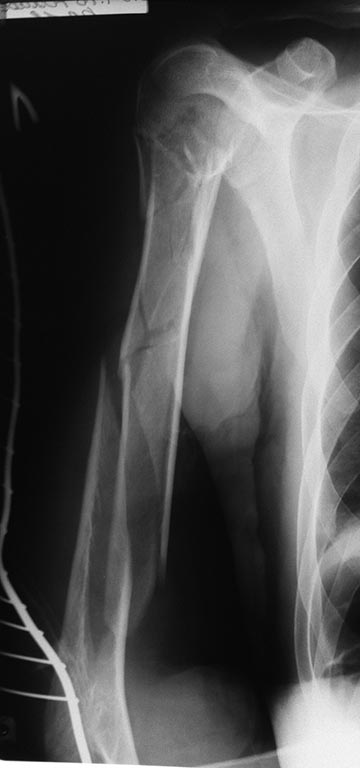

Здравствуйте, уважаемые коллеги! Прошу Вас поделиться мнением о наиболее приемлемой тактике лечения данного перелома плечевой кости.

Пациент - пожилой мужчина, 61 года, с закрытым оскольчатым переломом плечевой кости на всех уровнях (снимок прилагается). Травма в результате ДТП от 23.04.16г. Монотравма. Соматическая отягощенность, выражается наличием оперированного C-r желудка (резекция) в 2014г. Состоит на учете у онколога, но серьёзных беспокойств по этому поводу нет. В общих анализах ничего не смущает. Для оценки перелома головки плеча, КТ пока не доступна. Но наверняка перелом головки плеча больше чем 2х-фрагментарный.Если оперировать, то пластиной думаю слишком травматично. Если штифтовать, то не знаю получится ли прихватиться 2 винтами в дистальном отломке (одного мне кажется не достаточно). Да и в проксимальном не все так просто.

Или все таки оставить в покое все эти мысли об операции, и попытаться лечить по Сармиенто? Но и здесь, как говорится: "консервативное лечение - это тоже лечение"! Пациент из глубинки - из города в 80 км от нашего ЛПУ, а там, по обыкновению. травматолог отсутствует.

Перелом проксимального отдела плеча здесь двухфрагментный, в смысле, даже если есть трещины в головке, бугорки остались на месте. В дистальном отломке достаточно одного переднезаднего винта. По снимкам с линейкой здорового плеча (с центрацией 1)на головку и 2)на дистальный отдел) надо точно подобрать гвоздь по длине.